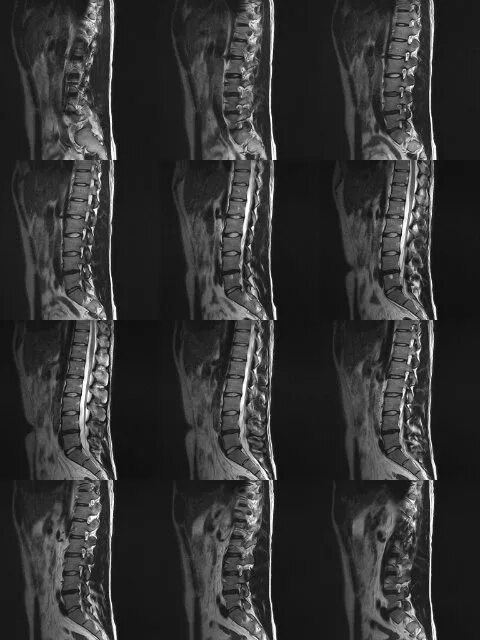

Спондилоартроз на уровне l1 s1